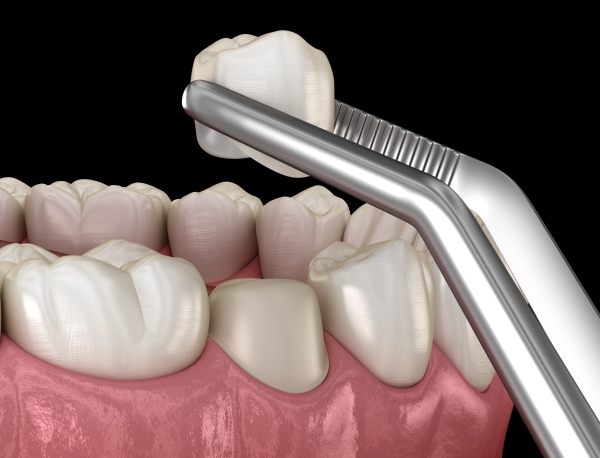

Bọc răng sứ

Bọc răng sứ là kỹ thuật nha khoa nhằm phục hồi hình dạng, chức năng và thẩm mỹ răng bị tổn thương nặng, mòn men hoặc hư hỏng do sâu răng, áp dụng cho những răng đã trám nhiều lần hoặc bị gãy vỡ lớn. Đây cũng là phương pháp giúp giảm cảm giác ê buốt đáng kể, đặc biệt trong các trường hợp răng yếu, nhạy cảm hoặc đã điều trị tủy thành công.

Quá trình bọc răng sứ gồm mài nhỏ phần men răng gốc để tạo khoảng trống, sau đó lắp mão sứ phù hợp về màu sắc, hình dáng và kích cỡ. Công nghệ này đảm bảo chiếc răng có độ chính xác cao, khả năng chống mòn, chống mài mòn và chịu lực tốt, duy trì thẩm mỹ lâu dài.

Bọc răng sứ không chỉ giúp giảm ê buốt hiệu quả mà còn nâng cao tính thẩm mỹ, tự tin hơn trong giao tiếp. Để tránh các vấn đề không mong muốn, khách hàng cần chọn loại sứ phù hợp, đảm bảo quá trình mài răng thực hiện đúng kỹ thuật và vệ sinh răng miệng đều đặn sau khi phục hình.